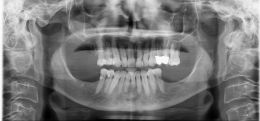

Implantologia classica e post-estrattiva

Posizionamento fixtures in tecnica a due tempi e postestrattiva

Impianti per la sostituzione dei denti e degli impianti affetti da parodontite in entrambe le arcate